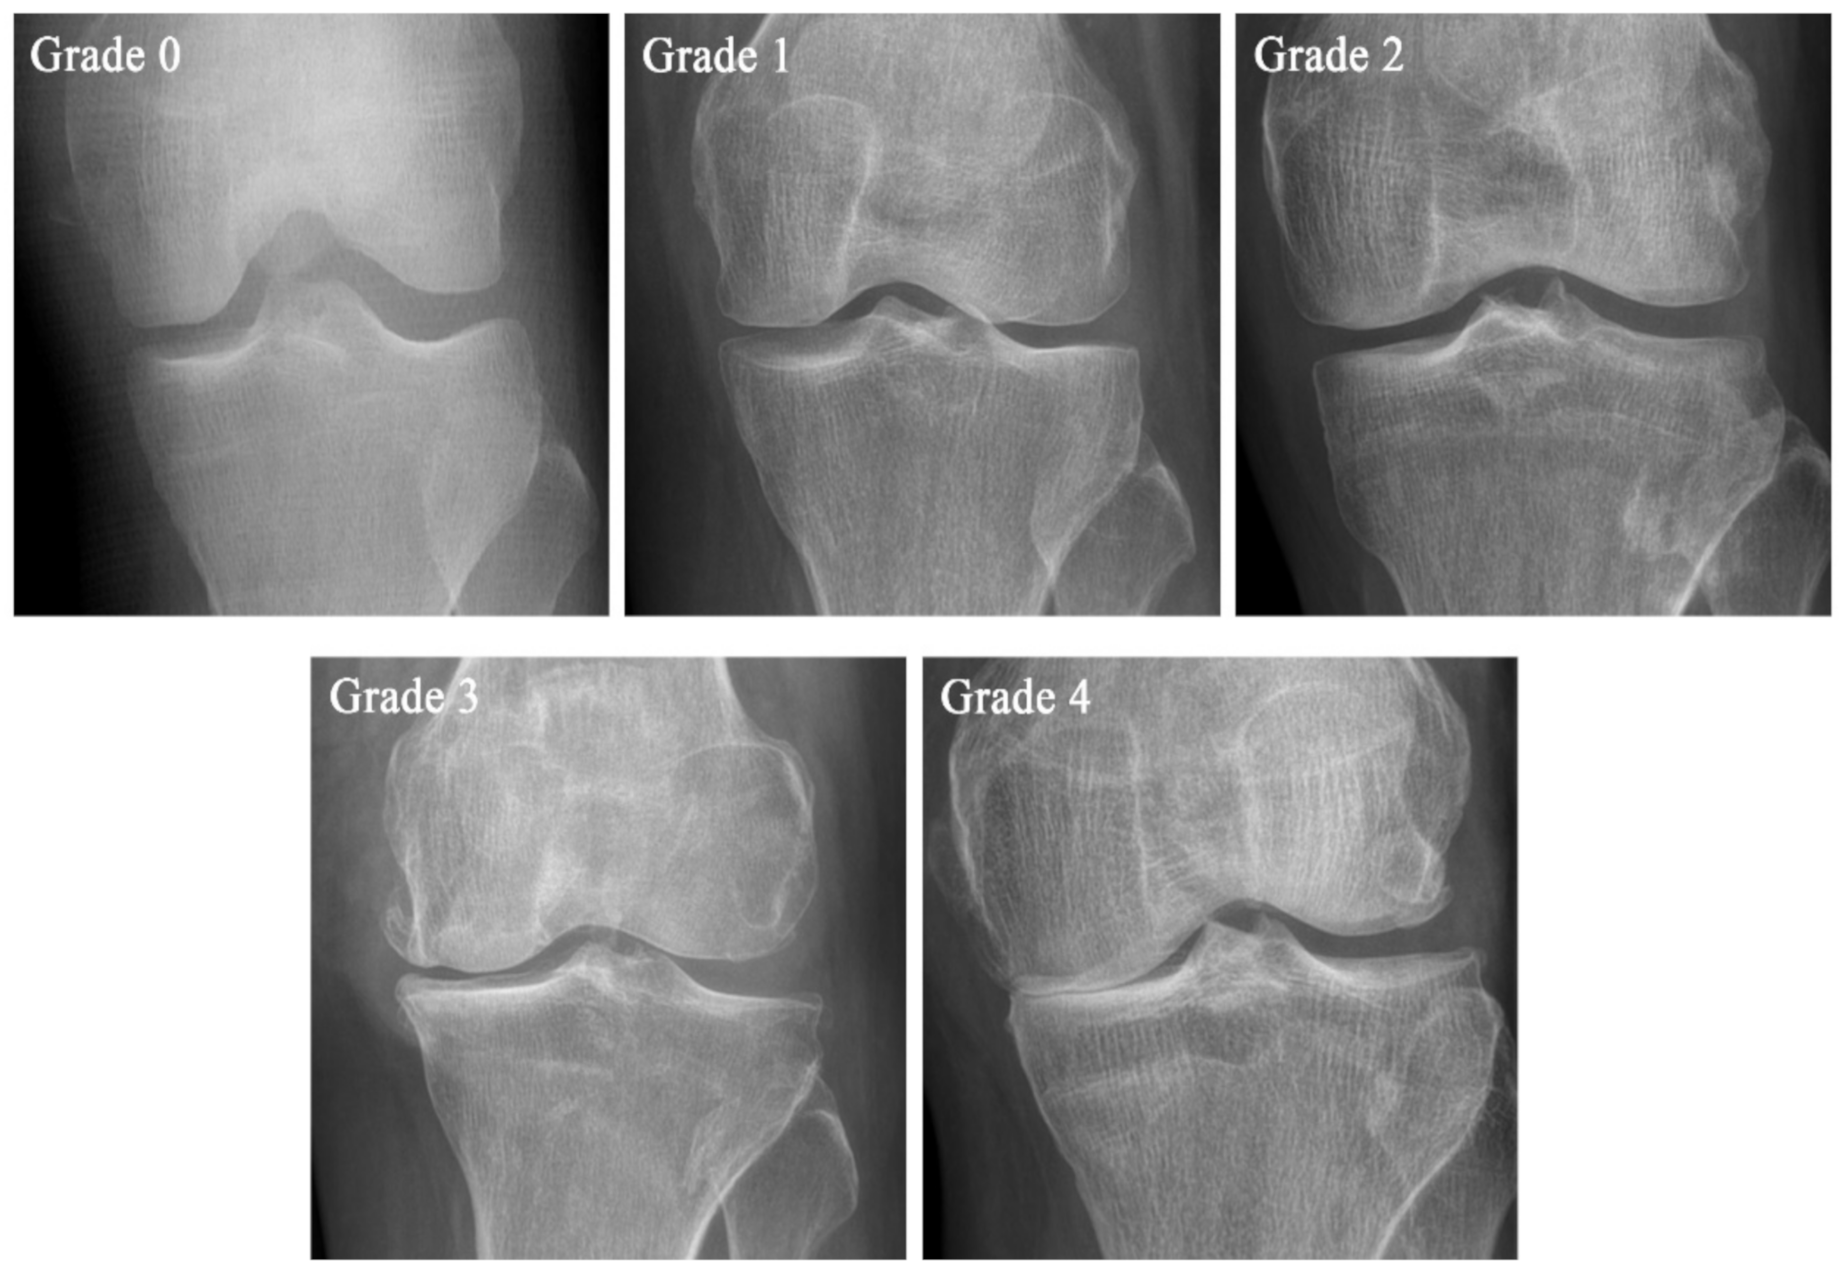

| Grade | KL Scale | Ahlbäck Classification | KOGS |

|---|---|---|---|

| Grade 0 | No pathological features of osteoarthritis (OA) | ||

| Grade 1 | Suspicious narrowing of the joint space and possible osseous lip | Joint space narrowing, with or without subchondral sclerosis. Joint space narrowing is defined by this system as a joint space <3 mm, or less than half of the space in the other compartment, or less than half of the space of the homologous compartment of the other knee | An isolated medial, lateral tibiofemoral, or patella-femoral joint OA with ligament stability and two functionally intact compartments |

| Grade 2 | Clear bone tissue and possible stenosis of the joint space | Obliteration of the joint space | Deteriorating isolated lesion with ligament stability and a correctible coronal subluxation |

| Grade 3 | Moderate multiple bone tissue, clear narrowing of the joint space, slight sclerosis, and possible deformity of the ends of the bones | Bone defect/loss < 5 mm | Includes an isolated medial or lateral tibiofemoral OA and concomitant pathologies such as anterior cruciate ligament deficiency (3A) or grooving of patella-femoral joint or patellectomy (3B) |

| Grade 4 | Large bone tissue, marked narrowing of the joint space, severe sclerosis, and clear deformities of the ends of the bones | Bone defect/loss between 5 mm and 10 mm | Includes cases of bi-compartmental tibiofemoral OA without concomitant ligament instability (4A) and with ligament instability (4B) |

| Grade 5 | Bone defect/loss >10 mm, often with subluxation and arthritis of the other compartment |